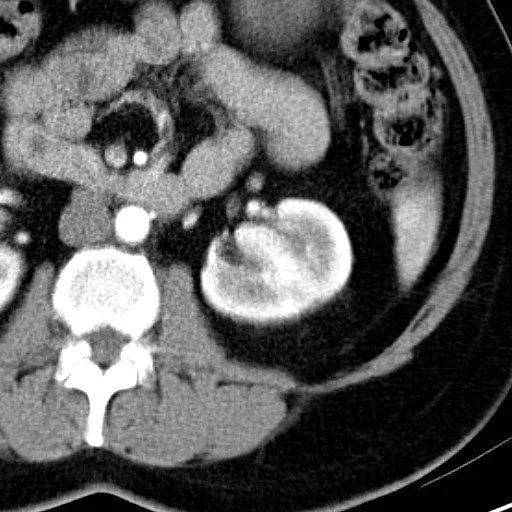

Lithium Nephrotoxicity

• Basically multiple bilateral renal cysts

• Duration of lithium therapy increases the risk of ESRD